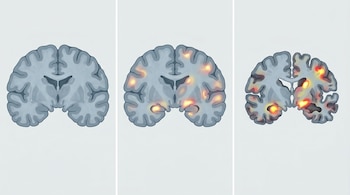

El análisis reveló tres cursos principales en el deterioro cognitivo: estabilidad, declive lento y declive rápido. Estos resultados se basan en el mayor seguimiento realizado hasta la fecha en personas sin síntomas iniciales, lo que permitió observar cómo evoluciona la enfermedad desde sus primeras etapas.

Uno de los hallazgos más relevantes es que cerca del 70% de los participantes permaneció estable durante aproximadamente seis años. Esto sugiere que una proporción importante de personas puede conservar sus capacidades cognitivas durante largos períodos, incluso en fases iniciales.

Los investigadores observaron que niveles elevados de esta proteína, junto con una mayor acumulación de tau en el cerebro y un menor tamaño del hipocampo —una región clave para la memoria—, se relacionaban con un deterioro más rápido o progresivo desde etapas tempranas.

Gracias a estos indicadores, el modelo desarrollado logró anticipar la evolución de los participantes con una precisión cercana al 70%.